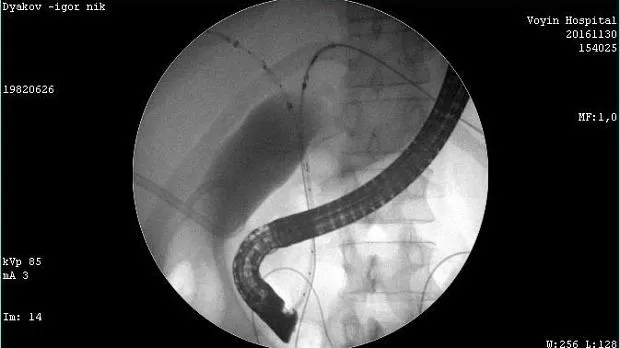

Молодой человек 33 г. Диагноз подтвержден. Стентирован пластиковыми стентами, потом самораскрывающимися. Одномоментно анте и ретроградно - с хорошим результатом. Дальше был поставлен в очередь на трансплантацию. Дальнейшая судьба не известна.